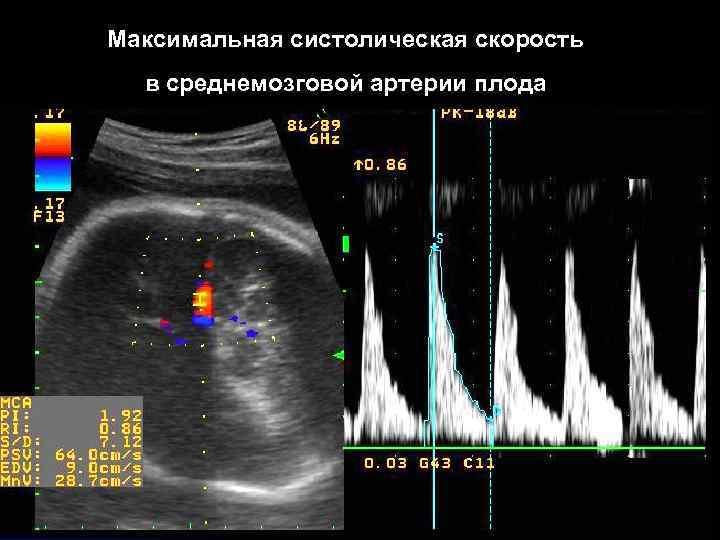

Максимальная систолическая скорость в среднемозговой артерии плода

Допплерометрия- один из основных методов неинвазивной оценки гемодинамики плода. l При развитии анемии у плода показатели кровотока в AU(маточные артерии)и UA(артерия пуповины) могут быть в пределах нормы. l Анемия у плода ассоциируется с повышенным сердечным выбросом, повышенным кровотоком в вене пуповины, нижней полой вене, нисходящей аорте и средне - мозговых артериях плода.

1995 г. - проспективное исследование оценки максимальной систолической скорости кровотока(PSV) в средне-мозговой артерии плода (MCA) с целью диагностики развития анемии (Mari et al. ) 2000 г. - мульти- центровое исследование соотношения уровня фетального гемоглобина и показателей максимальной систолической скорости кровотока(PSV) в средне-мозговой артерии плода (Mari et al. ) 2002 г. - проспективное исследование 125 случаев изоиммунизации: повышение максимальной систолической скорости кровотока(PSV) в MCA более 1. 5 Мо. М имеет : l чувствительность 88%, l специфичность 87% в определении средней тяжести и тяжёлой степени анемии у плода.